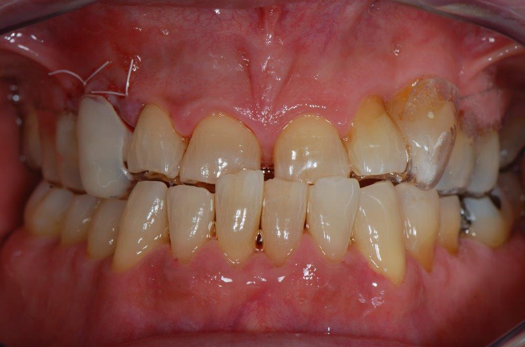

Fig 16. Final restorations (15 weeks postoperatively).

Figure 16

The final impression appointment follows the light-load phase, provided the implant is stable and the soft tissue is acceptable to the clinician. Polyvinyl putty and light-body impression materials were used in this case; analog casts and final full-zirconia full crowns were fabricated (Figure 16). The patient provided feedback that chewing was comfortable and without food impactions. Keratinized gingival cuff was developed, and natural-tooth contours for the restorations mimicked what is normally found in human dentition. The healed bone surrounding the ceramic dental implant was similar in density and crestal levels in comparison with the adjacent natural teeth, evident in the radiographic evaluation (Figure 17). Final long-term restorations at the gingival crest and restoration interfaces were also consistent in optimum periodontal health and gingival height. Arch-form integrity was upheld and occlusion was managed; osseointegration and light-load principles optimized the success of the restorations, and an acceptable, harmonious esthetic outcome was achieved for the patient.